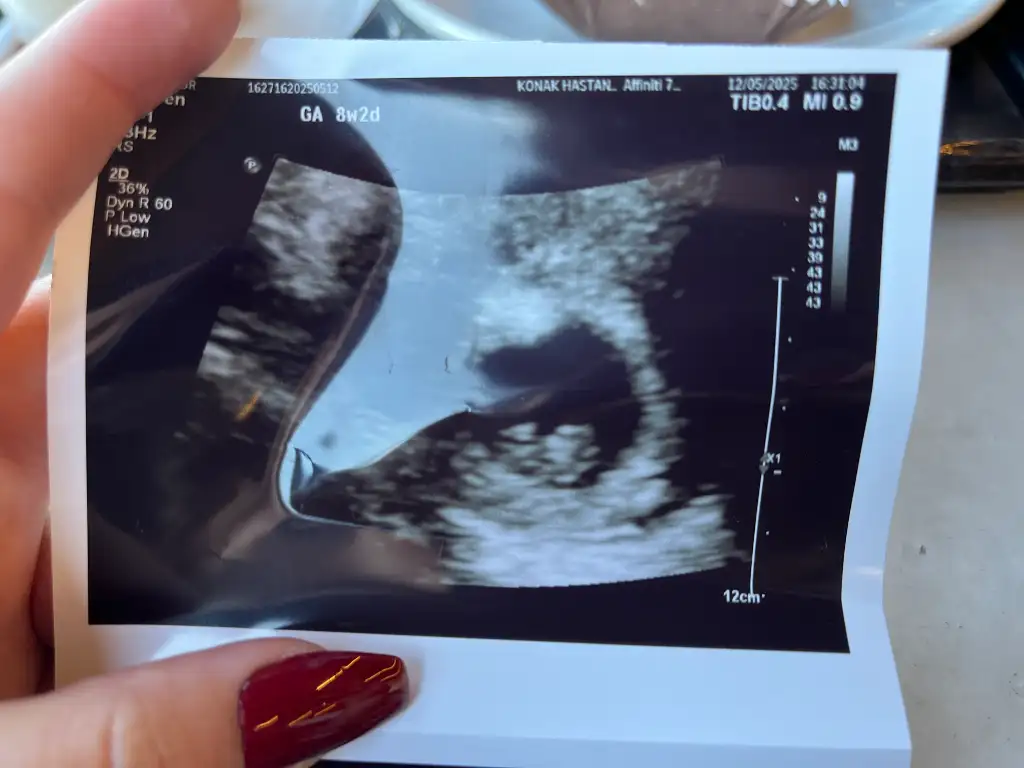

Kızlar merhaba 6+5 benim ultrasonuma da bakar mısınız birinci fotoğraf Vajinal çekildi ikinci fotoğraf karından çekildi

Eklentiler

• IMG_3687.webp

40,2 KB · Görüntüleme: 27

• IMG_3685.webp

21,2 KB · Görüntüleme: 25